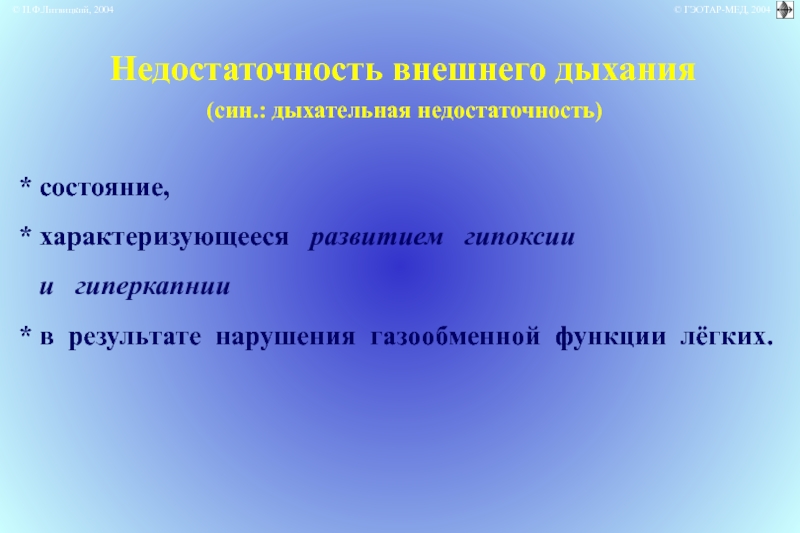

Роль легких в метаболических процессах